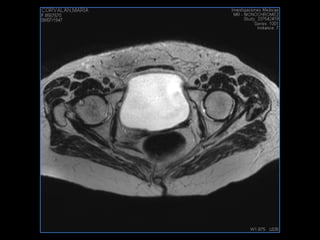

PROTOCOLO pelvis SAG T2, Y FAT SAT (FINOS) AXIAL T1  AX FAT SAT CON   GADOLINIO :  AX T1 Y COR T1 SAT: NO  FASE: RL THK: 3MM  COIL:  GAP: (FACTOR 1.4) 1MM FOV: 40 CM NEX:2 SINCRONIZACION RESPIRATORIA EN 3 O 4 CICLOS ALE